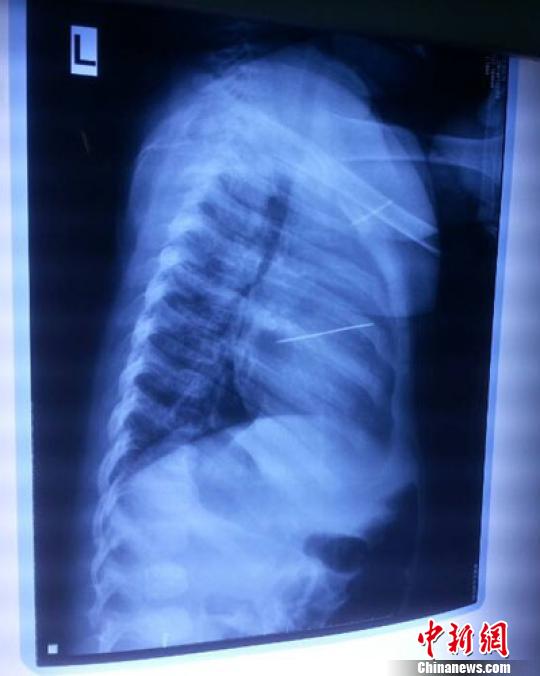

女?huà)胄仄崾拘呐K里面扎了一個(gè)縫衣針 蔡迅翔 攝

醫(yī)院胸心外科主任翟波介紹說(shuō),1月22日,小患者彤彤因?yàn)榘l(fā)燒抽搐來(lái)醫(yī)院就診,常規(guī)檢查時(shí)發(fā)現(xiàn)孩子心臟里面扎了一個(gè)縫衣針。

“第二天上午,我們做了個(gè)緊急彩超檢查,發(fā)現(xiàn)針是從患者右心室表面刺入,穿破室間隔,到達(dá)左心房,中間還有一部分損害到二尖瓣。于23號(hào)下午,我們就做了一個(gè)緊急手術(shù),手術(shù)中發(fā)現(xiàn),這枚針已經(jīng)刺入心臟,沒(méi)入了右心室的下面,表面已經(jīng)看不到針了,僅能看到一個(gè)小針眼,還在往外滲血,一點(diǎn)一點(diǎn)的滲,心包腔里面大概有100多毫升的出血,心包上一個(gè)洞,針在右心室表面刺入以后,穿過(guò)室間隔,在二尖瓣的上方,進(jìn)入了左心房,在針的四周,有很多纖維沉積物,包繞著這枚針?!钡圆ㄕf(shuō),他們把針取出來(lái)以后,測(cè)量了一下,長(zhǎng)度大概是五厘米,同時(shí)發(fā)現(xiàn)這個(gè)針給患者左心房的后壁造成了一定的損傷,左心房的后壁已經(jīng)損傷了三分之二,還剩下有左心房的外膜,很薄的一層,如果這一層再破的話,這個(gè)孩子將會(huì)引起大出血,很快就會(huì)死亡。

“我們都是善良的人,怎么會(huì)遇到這種想不到的事呢?當(dāng)時(shí)一看到孩子胸腔片里面是金屬物,我就感覺(jué)天旋地轉(zhuǎn)的,這個(gè)事刺激太大了,難以接受?!蓖疇敔敻鹦脑刚f(shuō),孩子太可憐了,恁小一點(diǎn)卻遭恁大的罪。